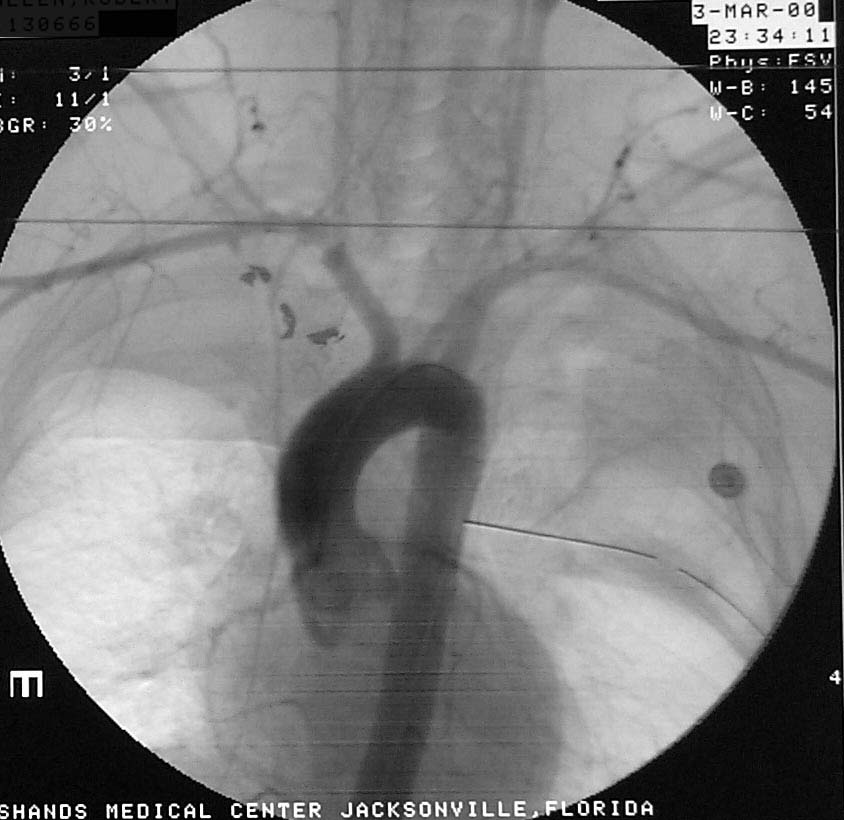

Enclosed are three figures--the CXR of a male with a left to right transmediastinal GSW of upper chest--no hard signs of vascular injury except for about 1000 cc blood out of left chest tube which eventually stopped without surgery. Next is angio #1 showing intimal defect in innominate artery right at the takeoff of the Rt subclavian and carotids. F/U angio one week later--no surgery--documents complete resolution of the intimal injury. There were no symptoms, including the blood from the left chest, attributable to this injury, thus fulfilling the criteria for observation.

Angio (1 week)